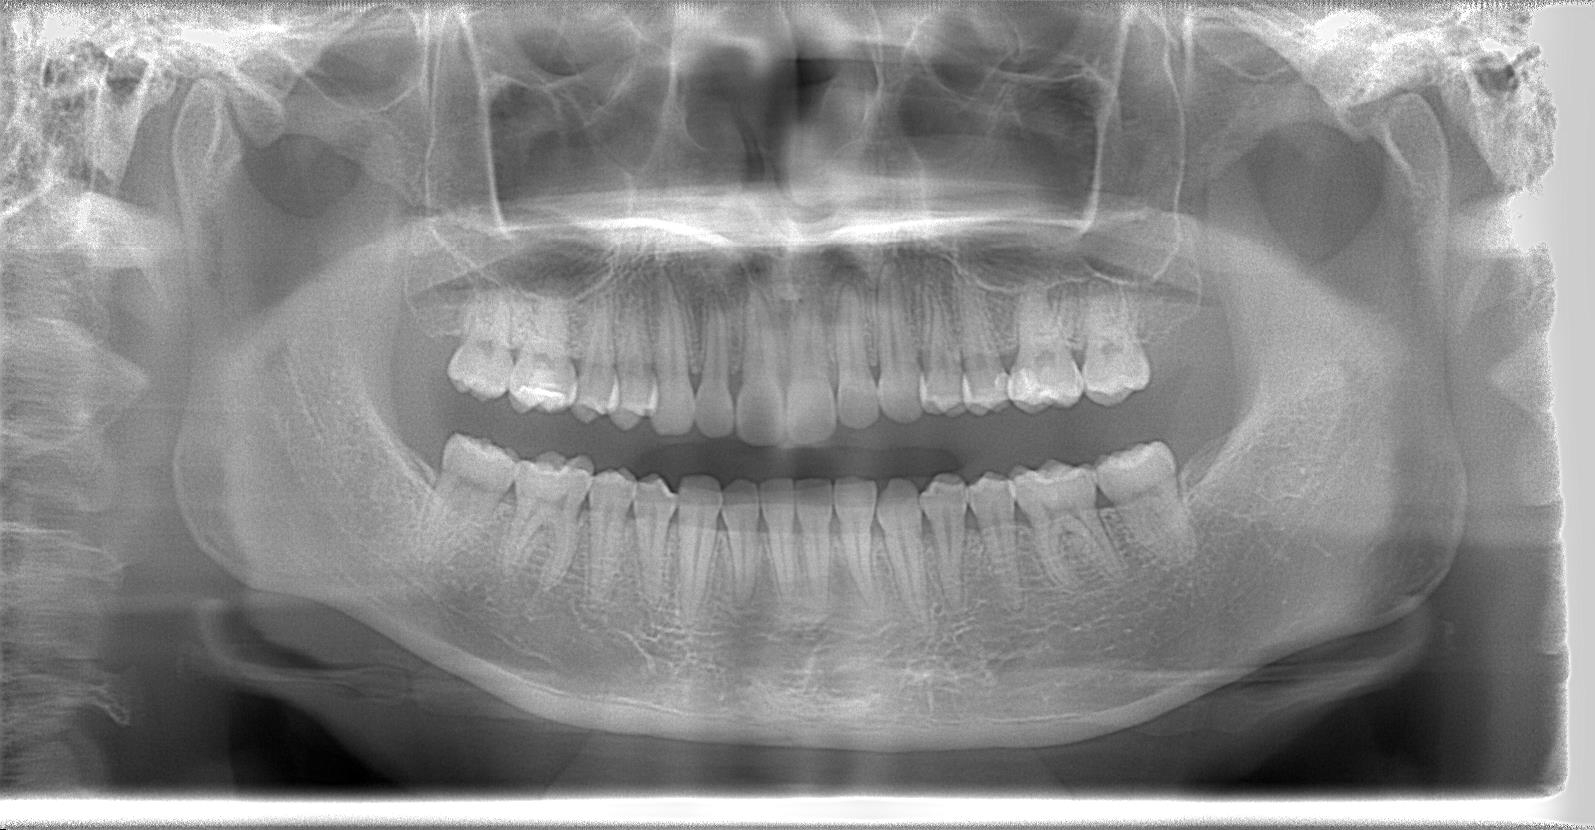

[術前パノラマレントゲン写真]

第3大臼歯を抜歯して矯正配列している症例です。